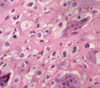

osteosarcoma.

There are characteristic atypical spindle cells with high nuclear-to-cytoplasm ratio associated with lacey osteoid